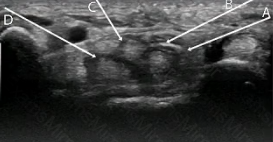

In this volar transverse image of the carpal tunnel, the arrows represent needles, and the arrowheads represent the needle tips. In planning a carpal tunnel corticosteroid injection with ultrasound guidance, which of the arrows combines the safest path through tissues with the BEST needle visualization?